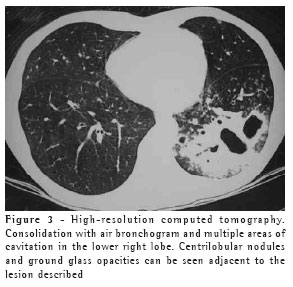

The most frequent finding in the imaging, present in the seven patients, was ill-defined consolidation (Figures 1, 2, 3 and 4). Five of patients presented air bronchogram, principally at the periphery of the lesion. In three cases, the consolidation was organized in the form of a mass. In six of the seven patients, irregular areas of cavitation were observed within the consolidations. Multiple cavitations were seen in five patients, and a singular cavitation was observed in one patient. In the patient presenting no cavitation, there were hypodense areas suggestive of necrosis (Figure 5). Only one of the patients presented air-fluid levels within the cavities.

Ground glass opacities, primarily surrounding the cavitated lesions, were reported in six patients, although this was not the predominant finding in any of the cases.

Small centrilobular nodular opacities presenting a 'tree-in-bud' pattern, predominantly encircling the area of consolidation, were observed in three patients. In one of those patients, the lesions were also found in the hanging portions of the lower lobes. Peribronchial nodules, tending toward confluence and located in the periphery of the pulmonary consolidations, were observed in four cases.

In our study, the principal pattern of pulmonary involvement was air bronchogram and cavitation, which was present in six patients. There were multiple cavitations in five cases and a singular cavitation in one. The consolidations were large and had irregular contours. The air bronchograms were located in the peripheral portions of the lesions. The pulmonary lobe most frequently involved was the upper right lobe, which was affected in four patients. Most of the case review studies confirm these findings.(2,5) Some studies have reported that, although cavitation might not be present at the time of diagnosis, it develops over the course of the disease.(4) In the sample evaluated in the present study, air-fluid levels within the cavitations were seen in only one patient.

Other findings were ground glass opacities, peribronchial nodules, small nodules of predominantly centrilobular distribution, and the "tree-in-bud" pattern. These alterations were predominantly seen surrounding the cavitated consolidations. In one case, they were also present in both of the lower lobes. It is believed that this finding indicates bronchogenic dissemination of the infection.